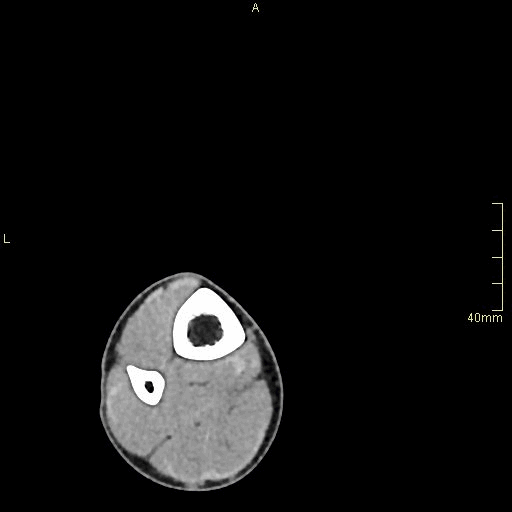

CT Ankle Non Contrast- Soft tissue window (axial)

REFERENCES